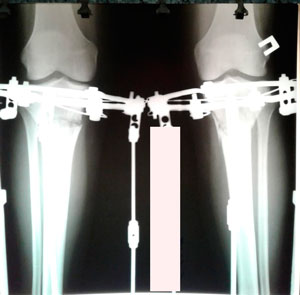

Рентген перед снятием аппаратов 85 дней

Дата операции - 11.10.2019.

Дата снятия аппаратов 14.01.2020

Срок сращения 93 дня.